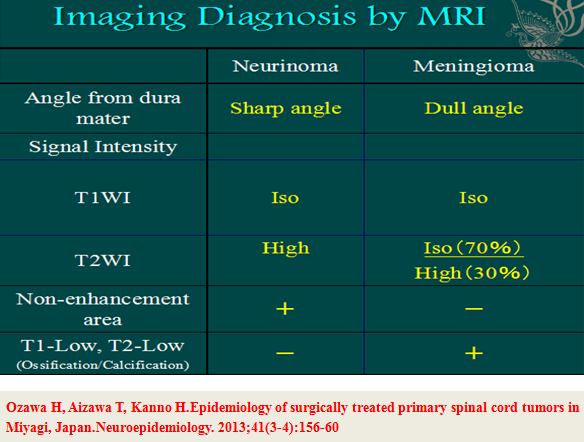

二、影像学表现:

X线平片和CT检查均需要依据钙化或肿瘤引起的明显骨质改变而检出病灶,阳性率较低,但是有助于了解脊柱的稳定程度、对手术方案的制定提供帮助;脊髓造影为有创性检查,通过肿瘤与造影剂的作用(如表现为充盈缺损等)对肿瘤的定位诊断有一定的帮助,但是对于肿瘤定性存在困难。MRI对椎管内软组织分辨率高并且能够避免骨骼的伪影,根据不同肿瘤相对特征性的MRI表现可以获得较为准确可靠的定位及定性诊断,有利于术前制定合理的手术方案。

神经鞘瘤(Neurinoma)

脊膜瘤(Meningioma)

我们回顾性分析了我院108例(111个病灶)硬膜下髓外肿瘤病例特点;神经鞘瘤69(70病灶),脊膜瘤31(31病灶),神经纤维瘤3(5病灶),畸胎瘤4(4病灶),转移性肿瘤1(1病灶)。不同肿瘤的MRI表现具有一定的特异性:

3.MRI上总结出的一些特点可以帮助术前预判;